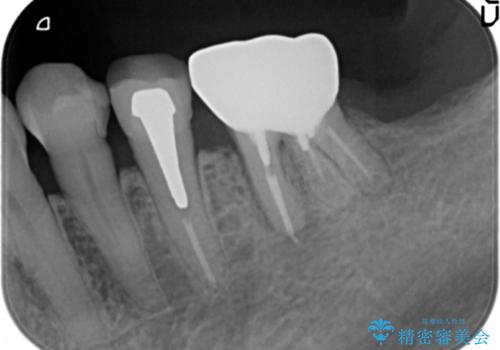

親知らずの移植 4年半経過症例 70代女性

- 親知らずの移植治療から4年半経過した患者様です。

他の歯の治療をご希望され、数年ぶりに来院して下さいました。

移植した親知らずは全く問題ないそうで、「まるで自分の歯のようです。本当にすごい技術ですね。」とおっしゃって下さいました。

歯肉の腫脹や退縮、動揺も認められませんでした。